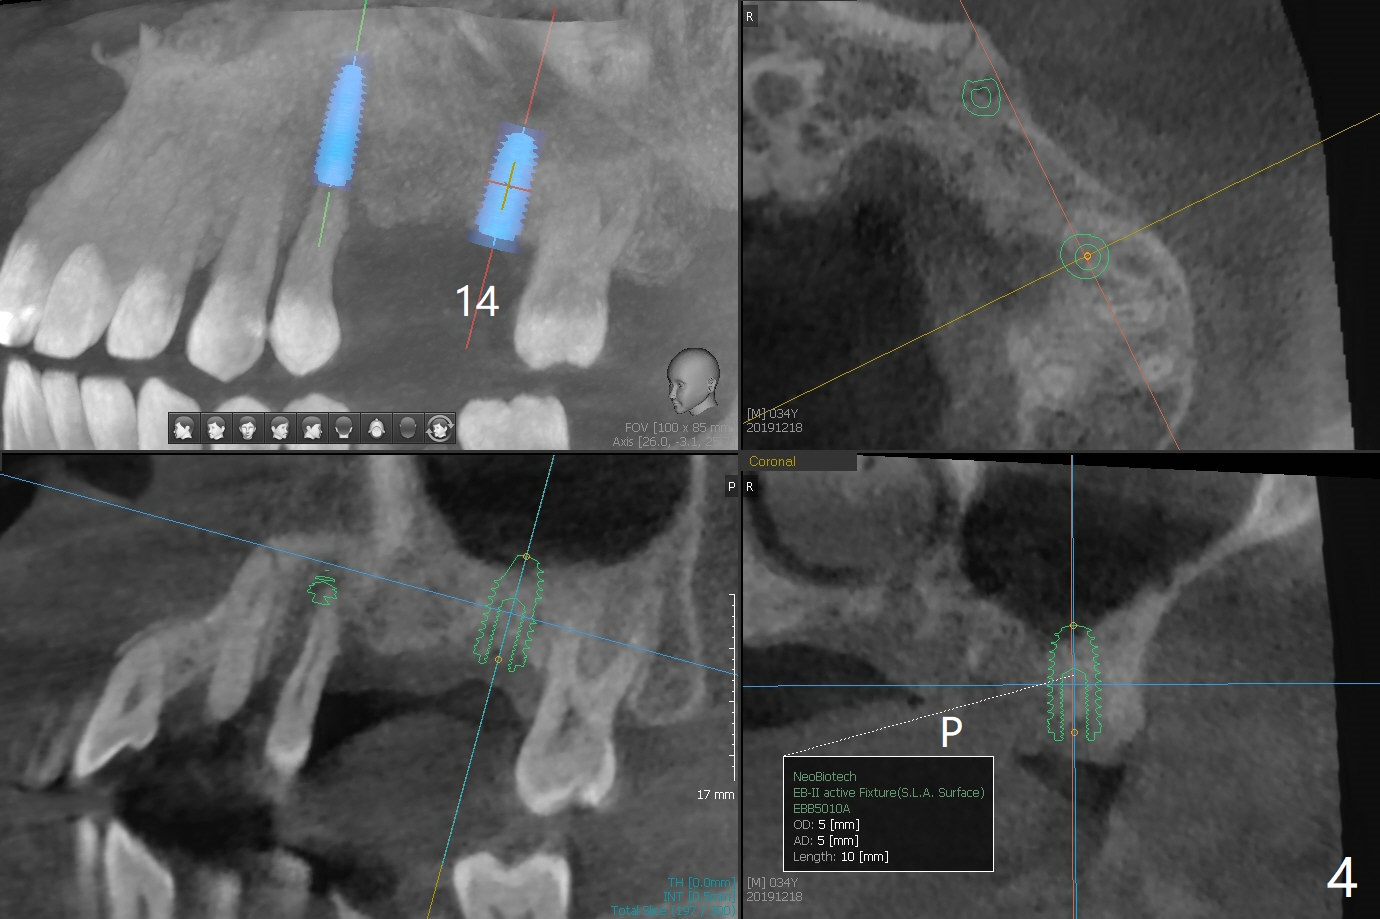

A 34-year-old man (smoker 1/2 ppd) presents to clinic for SRP and implant consultation (Fig.1). He wishes to restore UL first and the rest 2nd (Fig.2-5). Pay attention to placement level. OH will be emphasized, water pik and smoke cessation.